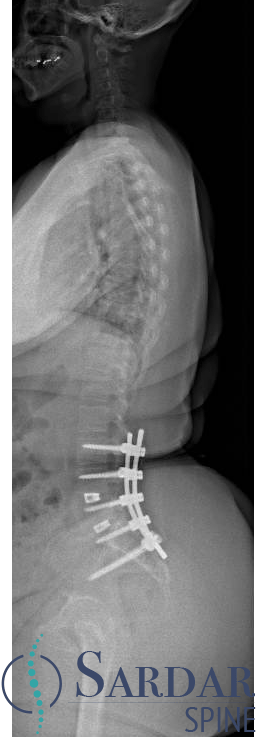

From robotics and AI-driven surgical planning to virtual modeling and custom implants, I’ve embraced a combination of tools that allow me to create tailored surgical plans for my patients—particularly those with scoliosis and spinal deformities.

What sets my approach apart is the seamless integration of these advanced technologies to ensure unparalleled accuracy and better outcomes for each patient.